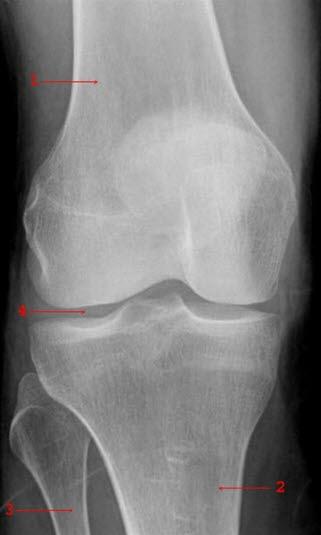

Røntgenbilde av kne - forfraDette er en tilstand som skyldes infeksjon med bakterier i ett, eller i enkelte tilfeller noen få ledd. Tilstanden kalles på fagspråket septisk artritt. Det er som regel store ledd, som for eksempel hofte-, kne- eller skulderledd, som blir rammet. Bakteriene kommer vanligvis fra et sår eller en underliggende infeksjonssykdom, og bakteriene sprer seg til leddet oftest via blodet.